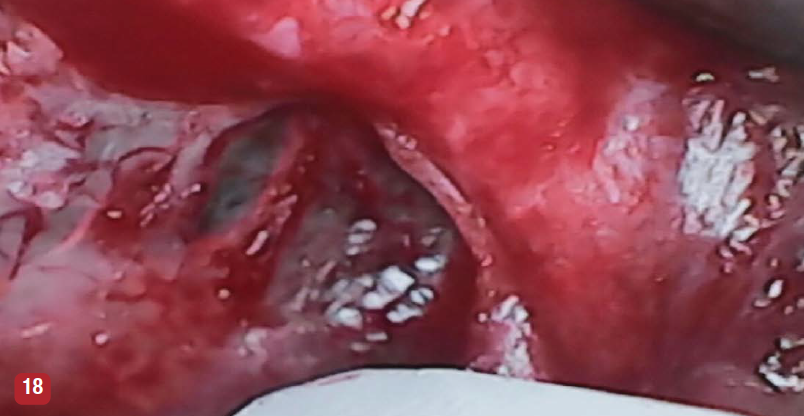

The dental videoscope was initially designed for use in regenerative periodontal procedures, and most published studies have reported on this aspect of its use. However, the videoscope is increasingly being used in other dental procedures. The videoscope is frequently used for improved visualization during surgical (Figure 16) and nonsurgical (Figure 17) endodontic procedures.16 For both applications, the videoscope is used in place of the surgical microscope. Unlike the surgical microscope, the videoscope can be easily maneuvered to a favorable angle to obtain different views of an endodontic treatment area and can be held by an assistant so that both the operator's hands are free. Another use of the videoscope is for sinus elevation surgery (Figure 18). The videoscope allows close-up visualization of the sinus membrane during elevation and close observation of the membrane during repair of any perforation of the membrane before bone grafting. The videoscope can also be used in prosthetic complications. Figure 19 shows a broken screw in an implant before removal. The videoscope allows detailed observations during removal of the screw fragment.